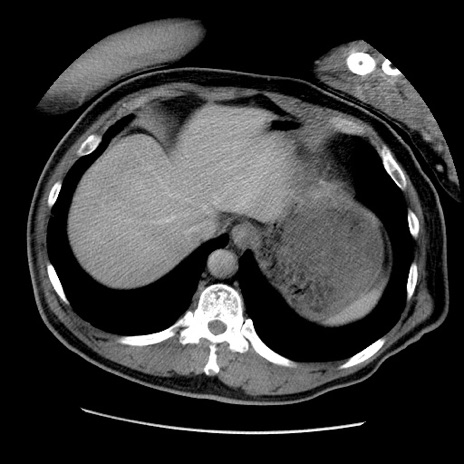

症例22(横断像)

【症例】50歳代男性

【主訴】腹痛

【現病歴】AVMからの被殻出血のため回復期リハ病棟入院中。 本日午後3時頃急に下腹部痛が出現した。

【既往歴】AVM、被殻出血、虫垂炎、高血圧

【身体所見】意識晴明、左半身不全麻痺、会話の理解は良好、36.5°C、腹部:膨隆、全体に板状硬、下腹部正中に圧痛点あり、反跳痛-、筋性防御不明、右下腹部にope scar

【データ】WBC 9400、CRP 0.06